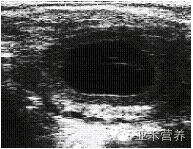

2.3 卵泡囊腫聲像圖

圖3顯示該病牛左側(cè)卵巢有卵泡存在,直徑在1.74 cm,B超圖像顯示為液性無回聲暗區(qū);右側(cè)卵巢有多個(gè)大小不一的卵泡存在。最大的卵泡直徑在3.9 cm,邊緣清晰,界限明顯。

卵泡囊腫聲像圖特征:卵泡囊腫病牛B超結(jié)果顯示卵巢體積增大,囊腫卵泡呈無回聲液性暗區(qū),卵泡直徑大于正常排卵卵泡直徑,卵泡內(nèi)部為一圓形無回聲液性暗區(qū),卵泡壁較薄,邊界整齊而光滑[6]。

圖3 卵泡囊腫聲像圖

Fig.3 An ultrasound image of a cystic graafian follicles